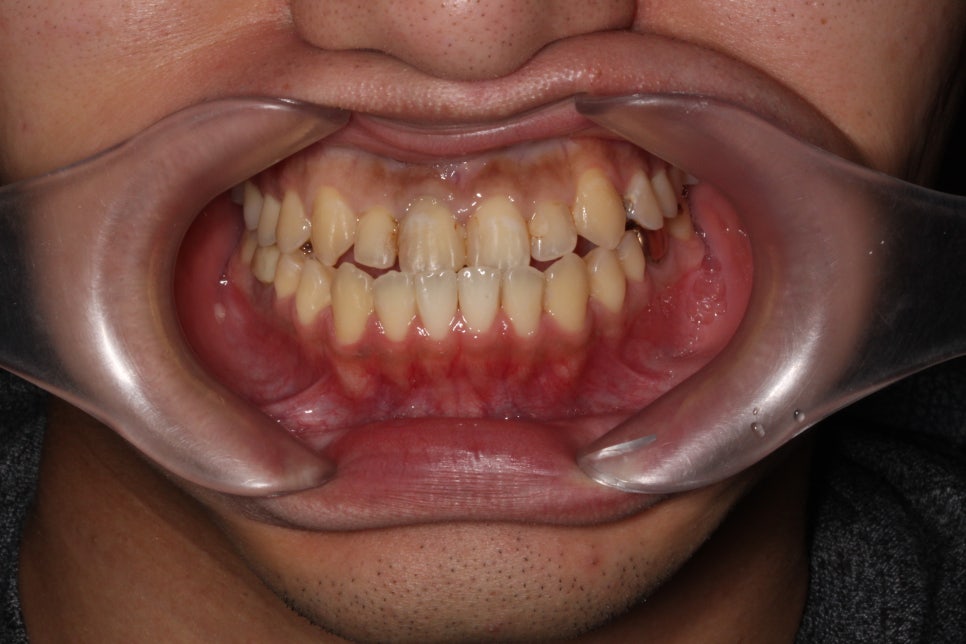

□ 앞니 마모

출처:투디 치과/ 앞니 마모 사례의 블링스 전후 사진입니다.

앞니가 마모되어 빈 공간이 많이 보이는

전 사진이 블링스를 만난 후 빈틈없이 자연스럽게

개선된 모습을 볼 수 있습니다.